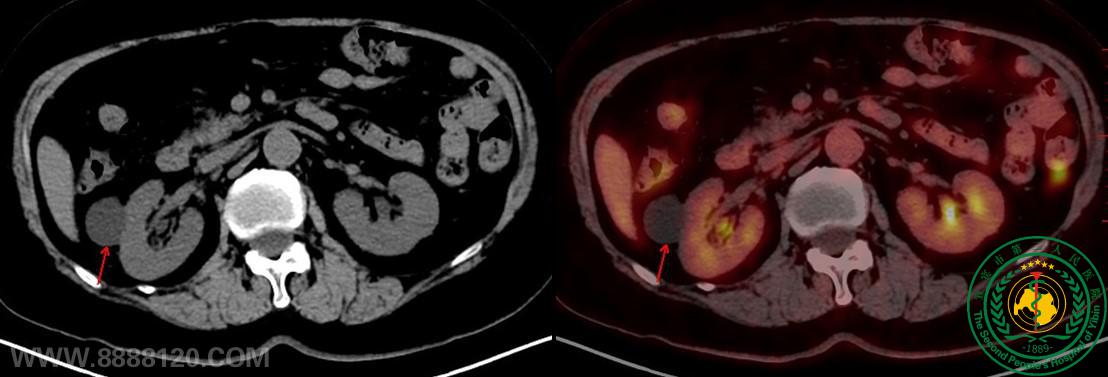

宜宾首例——华西宜宾医院核医学科顺利完成首例PET/CT检查

宜宾首例——华西宜宾医院核医学科顺利完成首例PET/CT检查52714